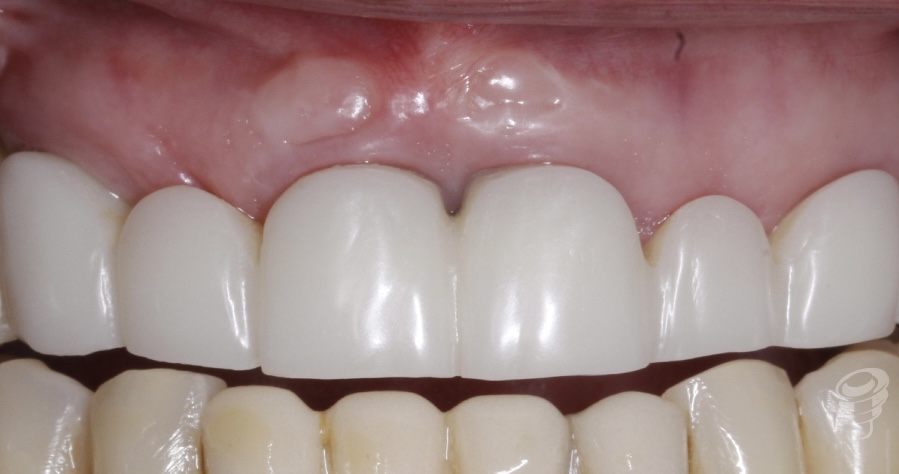

Resultado

Resultado de los perfiles de emergencia, situación estética gingival y protética de un PMMA que será el paso justamente anterior a la prótesis definitiva que se realizará en Zirconio monolítico.

Figura 18

Figura 19